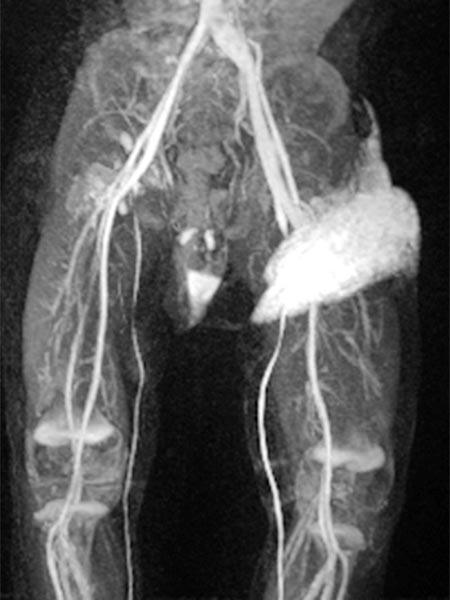

Contrast-enhanced dynamic MR angiography (coronal plane).

30 s after contrast injection in the early arterial phase, there is immediate early enhancement of the tumor in the left groin.

Contrast-enhanced dynamic MR angiography (coronal slice orientation).

41 s after contrast injection in the late arterial phase, there is further, rather diffuse, strong enhancement of the tumor ("tumor-blush") in the left groin, corresponding to a solid vascular tumor.

57 s after contrast injection in the early venous phase, the entire tumor continues to enhance strongly. The image now also displays a dilated early drainage vein in comparison of sides. The venous drainage (left iliac vein) has dilated because of the strong tumor perfusion with increased venous outflow.

130 s after contrast injection in the late phase, the strong enhancement of the tumor in the left groin remains, no early "wash-out". Additionally, the enhanced venous drainage via the left iliac veins still contrasts.